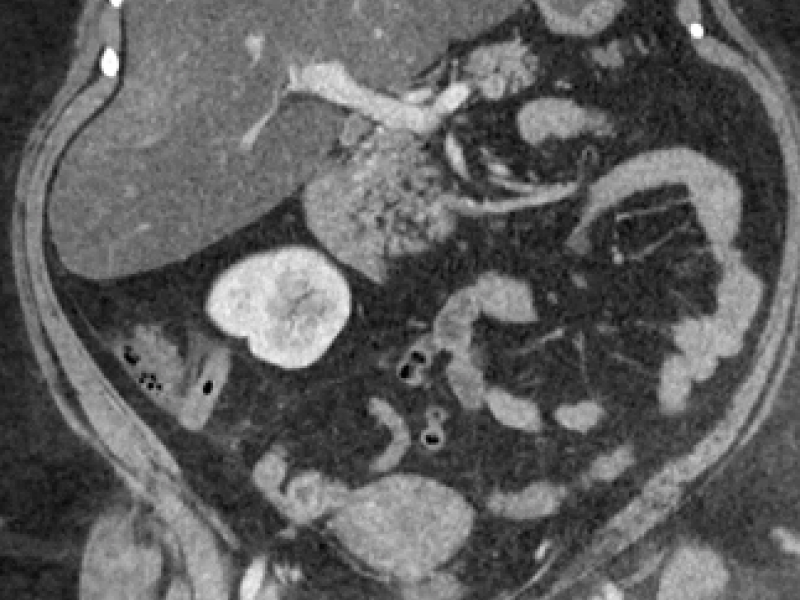

A 45-year-old female with a history of ovarian cancer

What's the Diagnosis? By Dr. Loran Hatch

40 yo F presents to the ED w/ 12 hours of GI symptoms. She